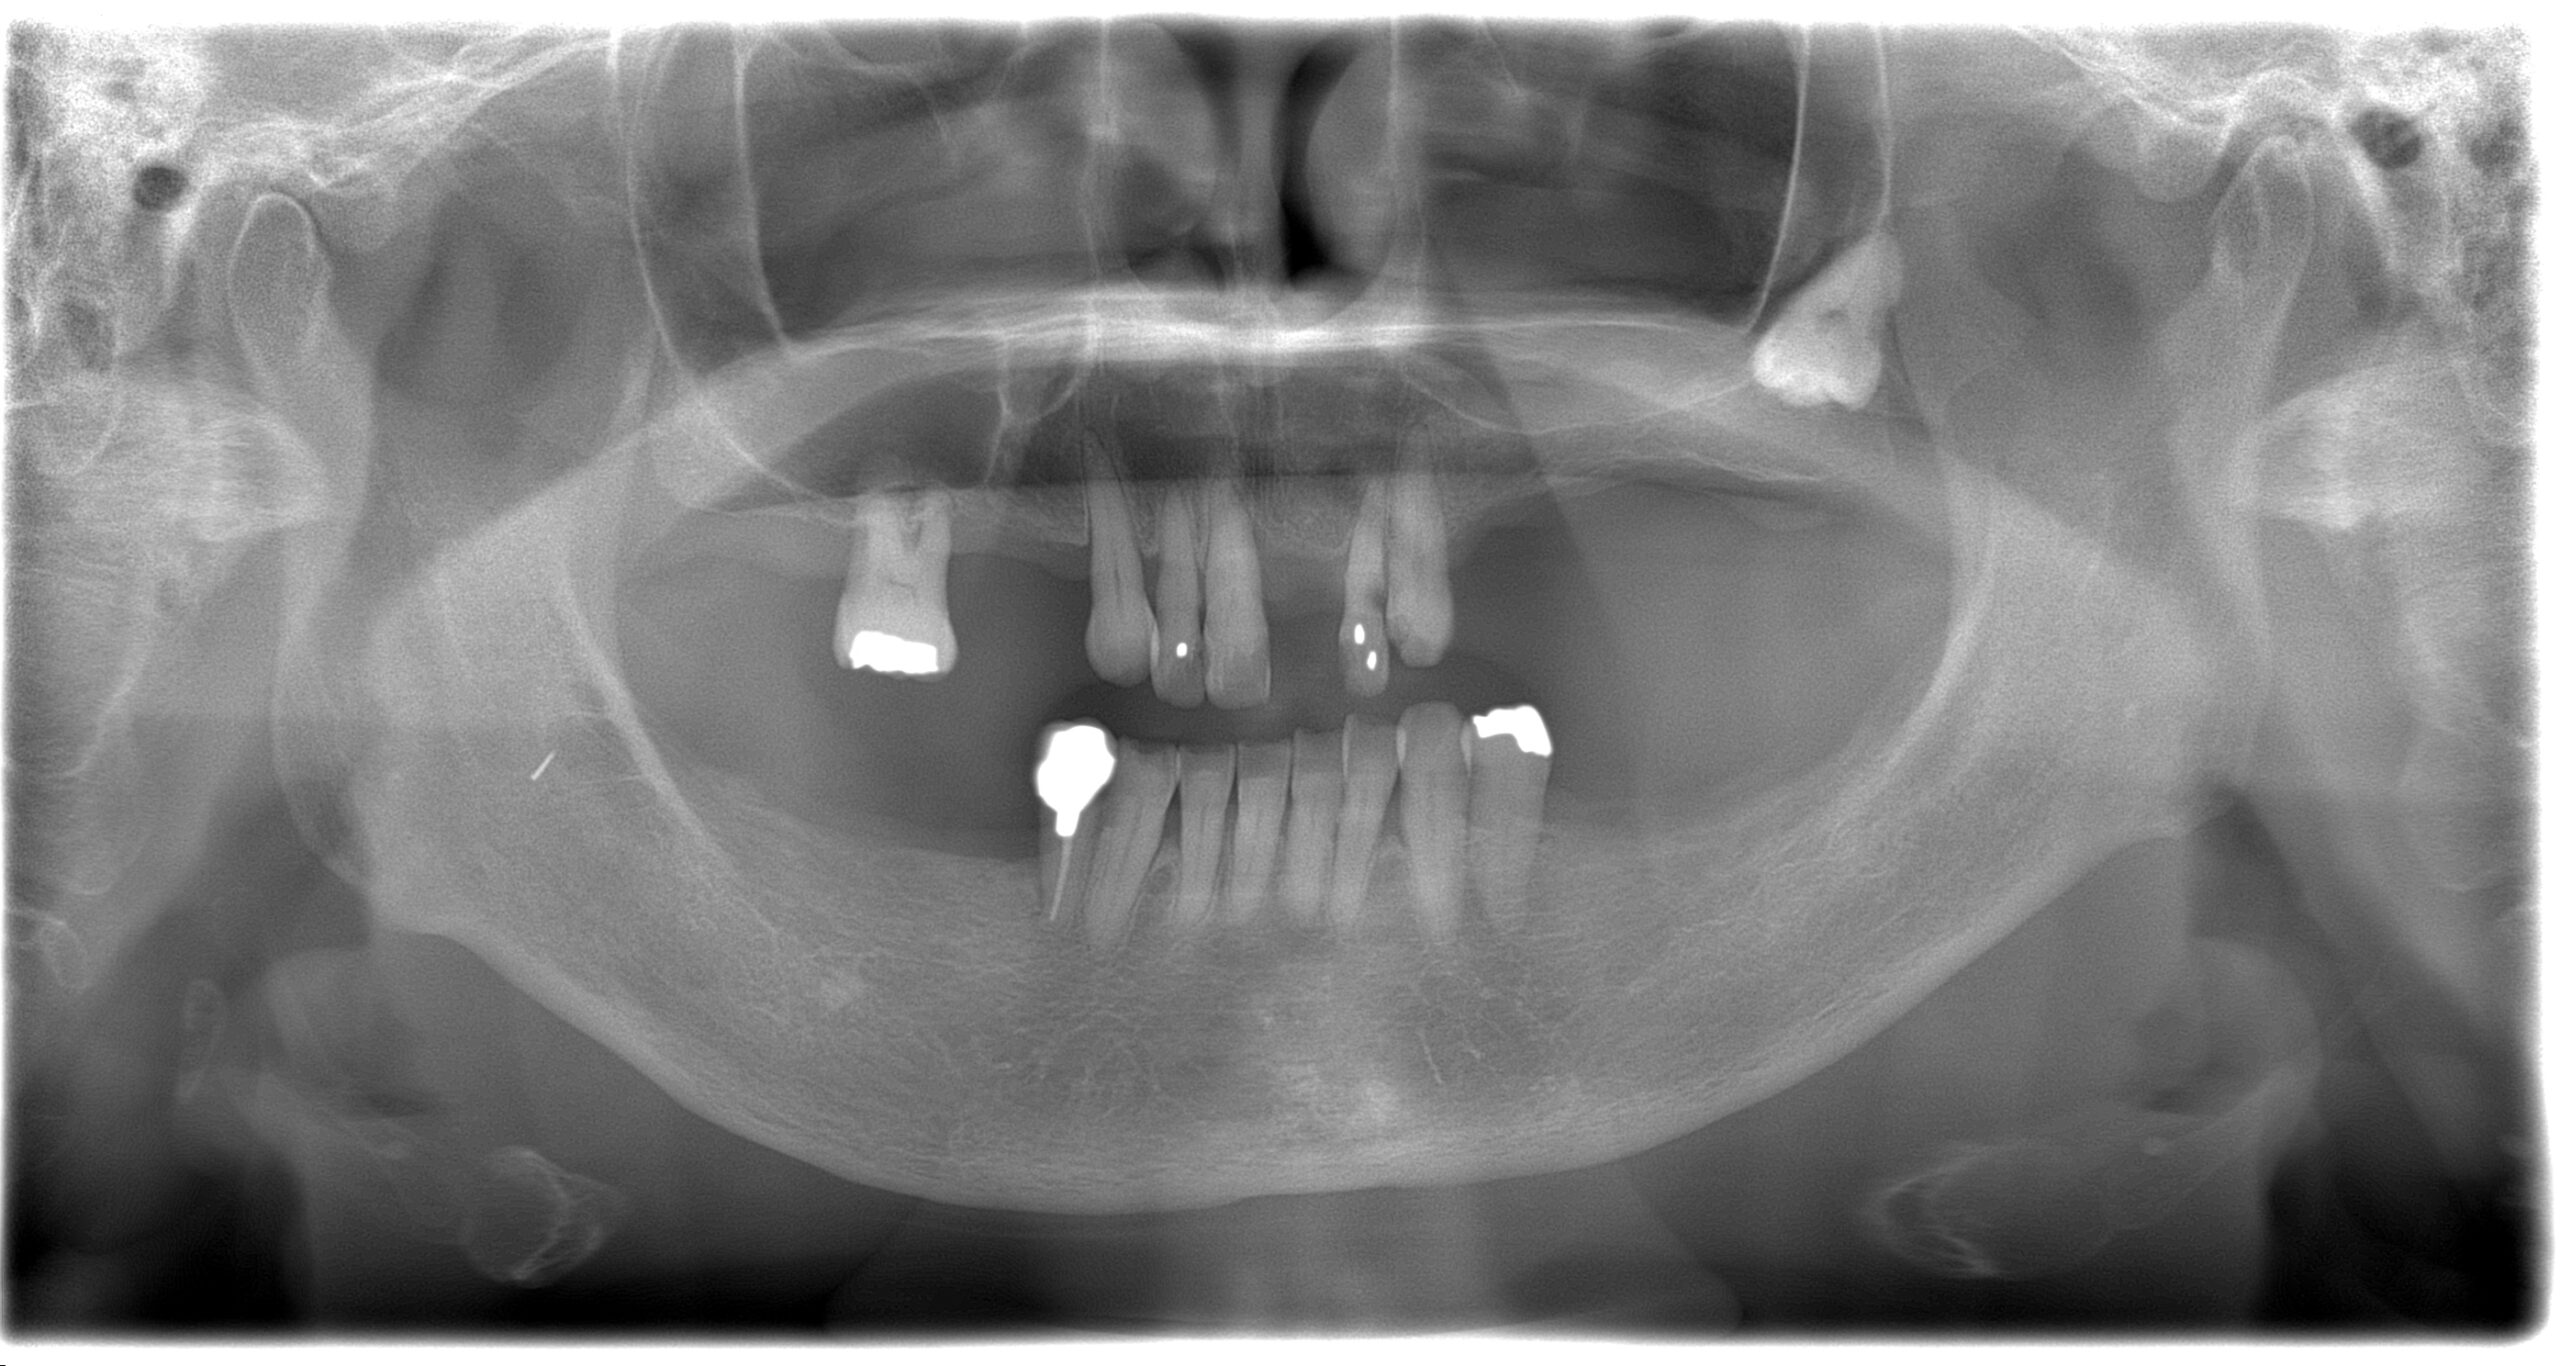

BEFORE

主訴

全体的に見た目を綺麗にしたい。奥歯でしっかり噛みたい。

診断名・主な症状

臼歯部欠損

年齢

65歳

治療内容

インプラント埋入(左下5・6,右下5・6,左上4・6)

サイナスリフト(左上4・6)

ジルコニアBr(右上6−左上3)

E –MAX CAD(右下4)

セラミックインレー(左下4)

治療期間/

通院回数

約1.5年/約20回

費用

インプラント治療 約2,000,000円

その他被せ物治療など 約1,000,000円

合計 約3,000,000円

*いずれも税込